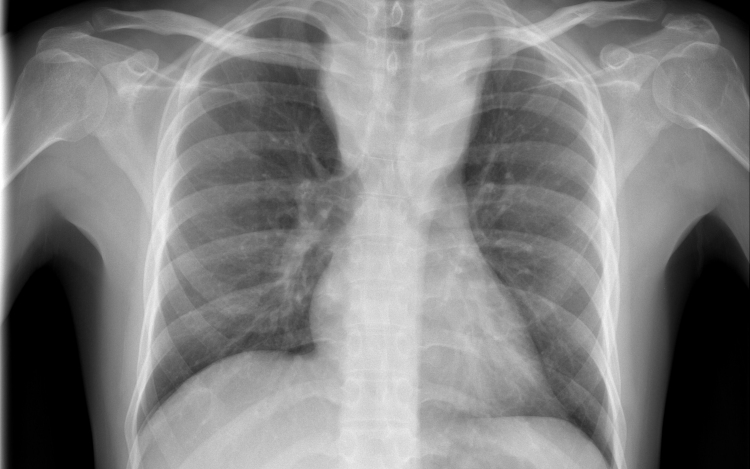

Forrás: mti - illusztráció

Tüdőrákban halt meg a transzplantáció után másfél évvel egy francia nő, akibe egy hajdan erős dohányos nő tüdejét ültették át.

A Lunc Cancer szakfolyóiratban megjelent tanulmány szerint az 57 évesen elhunyt donor 30 éven át napi egy doboz cigarettát szívott el.

A gyermekkora óta cisztás fibrózisban szenvedő páciens 2015 novemberében kapta meg a sokáig erősen dohányzó nő tüdejét, 2017 júniusában pedig bekerült a montpellier-i egyetemi klinikára, ahol két hónappal később elhunyt tüdőrákban, anélkül, hogy bármiféle terápiát alkalmazhattak volna nála. A tanulmány szerint a páciens a dohányzás okozta tüdőrák jellegzetes tüneteit mutatta.

A transzplantáció és a tüdő első rendellenességeinek röntgen általi észlelése közti rövid idő arra utal, hogy a tüdőrák már a donornál keletkezett, a szervkilökődés megakadályozására szedett immungyengítő gyógyszerek pedig csak felgyorsították a kifejlődését.

A tüdőrák hosszú lappangási idejére tekintettel a kutatók különleges elővigyázatosságot ajánlanak a dohányzó donoroktól származó szervek átültetésénél olyan esetekben, amikor a donor csak nem sokkal a transzplantáció előtt hagyott fel a dohányzással.